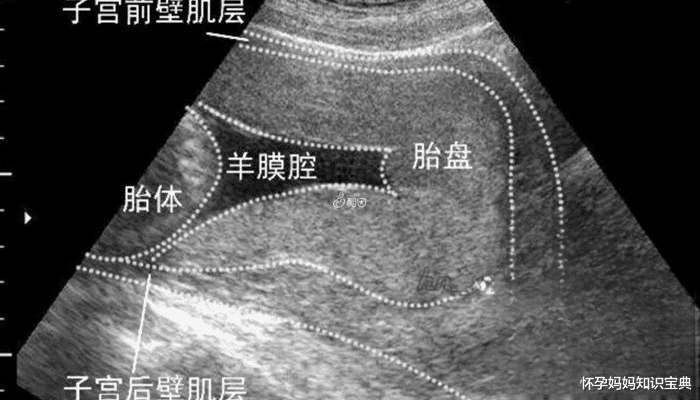

胎盘的位置分为前壁、后壁、左壁、右壁,据说,怀男孩女孩胎盘位置是不同的,怀儿子一般在前壁,后壁多是女儿,但也有说后壁儿子多于女儿的,其实胎盘位置与胎儿性别无关,只是受精卵在子宫的着床位置不同而已,所以说,前壁后壁看男女是不准的,没有科学依据,各位准爸妈不要当真!

但其实,胎盘前壁或后壁,是看不出男女的,胎盘后壁与前壁的区别主要是受精卵着床的位置不同而已。所以说,这种说法没有科学依据,不可信!前壁后壁看男女准不准虽然网传后壁多生女儿,前臂是男孩,但也有后壁儿子多于女儿的说法。其实这些都只是经验之谈,是不能准确判断胎儿性别的,胎盘前壁后壁与胎儿性别是没有联系的。胎儿的性别在受精卵结合的那一刻就已经确定了,而不是胎盘的位置来确定的。